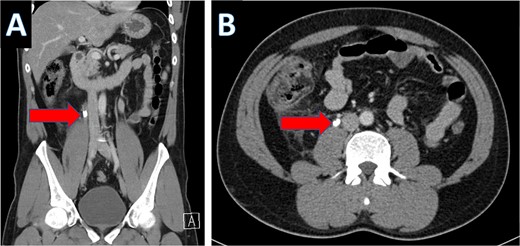

An IV contrast-enhanced CT scan of the abdomen and pelvis revealed an 8-mm proximal to mid-ureteral obstructive stone on the right side (Fig. 1), causing severe hydronephrosis of the right kidney and proximal hydroureter (Fig. 2).

CT scan showing right ureteral calculus (A: coronal; B: axial).